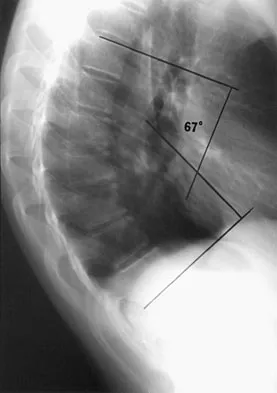

A 24-year-old professional football player underwent surgery for a symptomatic cervical disk herniation with radiculopathy 9 months ago. A current radiograph is shown in Figure 17. He has normal neurologic findings, no pain, and full range of motion. A CT scan shows a solid fusion. When can he expect to return to play?

The radiograph shows that the two-level anterior cervical diskectomy and fusion has healed. In addition, the patient has good range of motion and the neurologic examination is normal. Based on these findings, the patient can return to play immediately. Patients with one- or two-level anterior cervical diskectomies and fusions that have healed fully can return to play. Any loss of motion, persistent neurologic deficit, or significant adjacent segment degeneration may preclude a player from returning. Thomas B, McCullen GM, Yuan HA: Cervical spine injuries in football players. J Am Acad Orthop Surg 1999;7:338-347.